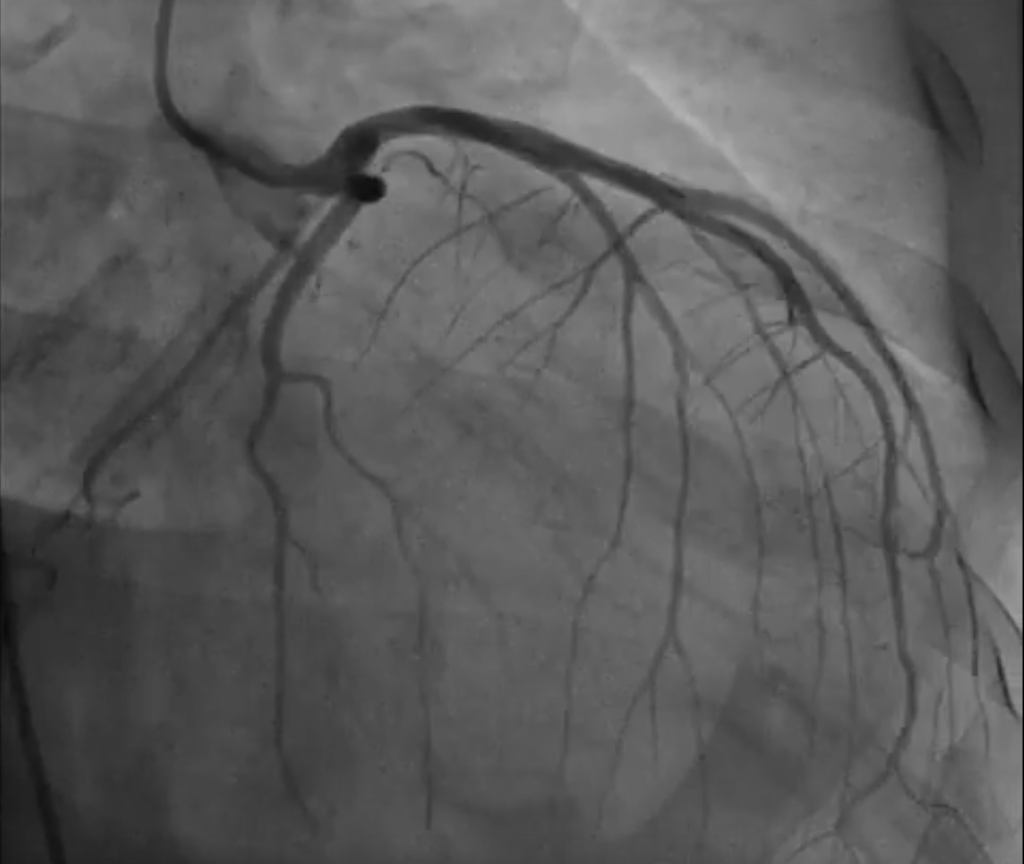

Un aneurisma del ventrículo izquierdo se define como una área de cicatriz miocárdica que presenta una forma bien delimitada y que, durante la sístole, experimenta un abultamiento inusual, lo que…